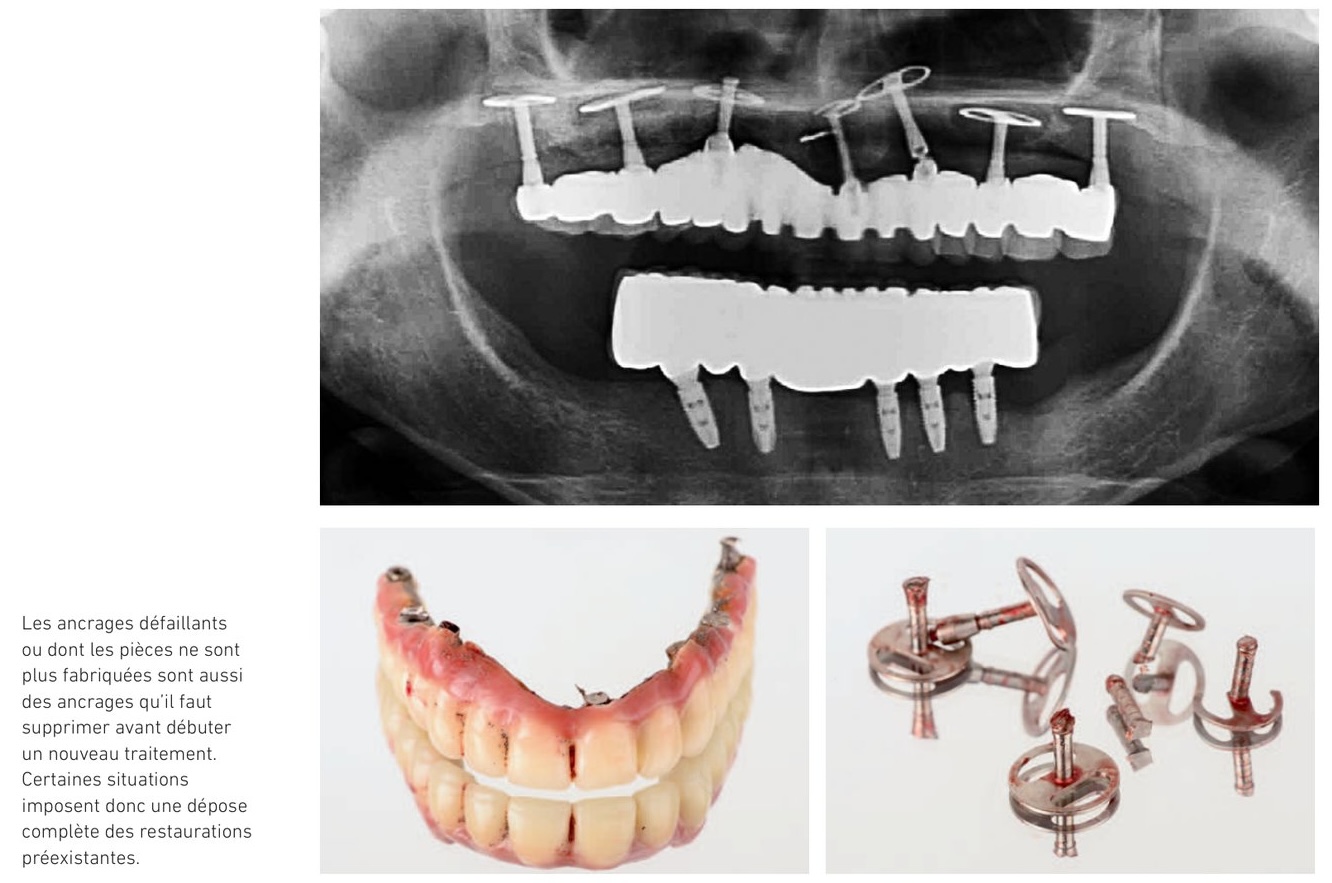

Disponibilité présente et future des pièces implantaires

Il faut ensuite s'assurer que le système implantaire utilisé est un système connu et que les pièces permettant de restaurer les implants sont bien disponibles et le seront dans le futur. À ce titre, des bases de données utilisant l'intelligence artificielle comme Spotimplant s'avèrent précieuses et efficaces pour aider les praticiens qui sont souvent démunis face à ces situations où le patient ne possède pas la traçabilité de ses implants.

Tout système implantaire dont les pièces prothétiques ne sont pas disponibles ou ne peuvent pas être identifiées indique la dépose de l'implant dans la mesure où la prothèse actuelle ne peut pas être maintenue en place.